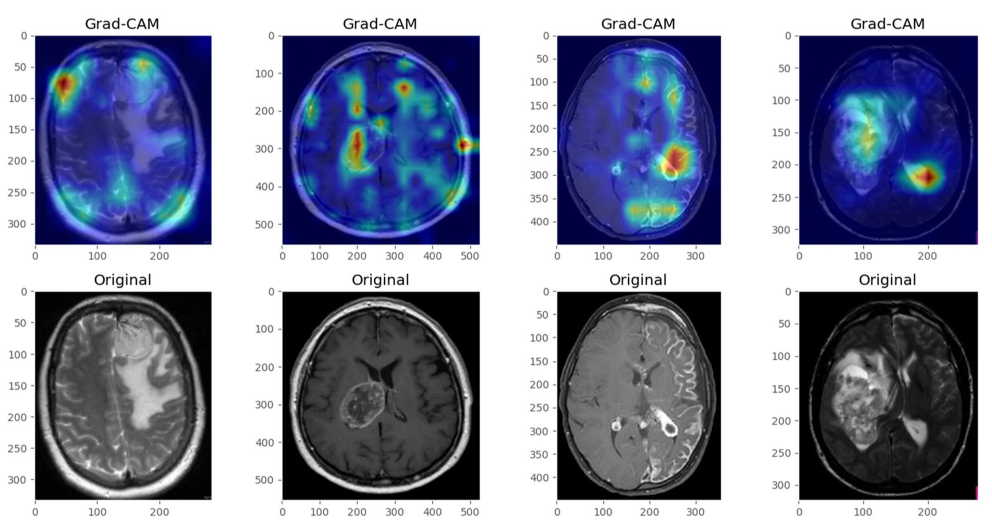

Looking at Figure 8, you can see how the pixels that contributed to the positive diagnosis have been highlighted. Along with the classification, this provides more actionable information. That is, the doctor can confirm the classification, explain where and how severe the tumour is and begin to understand the best course of action.

![Grad-CAM visualisation showing the areas of the brain that have contributed to positive tumour diagnosis (source: [5]).](https://adataodyssey.com/wp-content/uploads/2026/03/grad_cam_brain_tumor_wp.png)